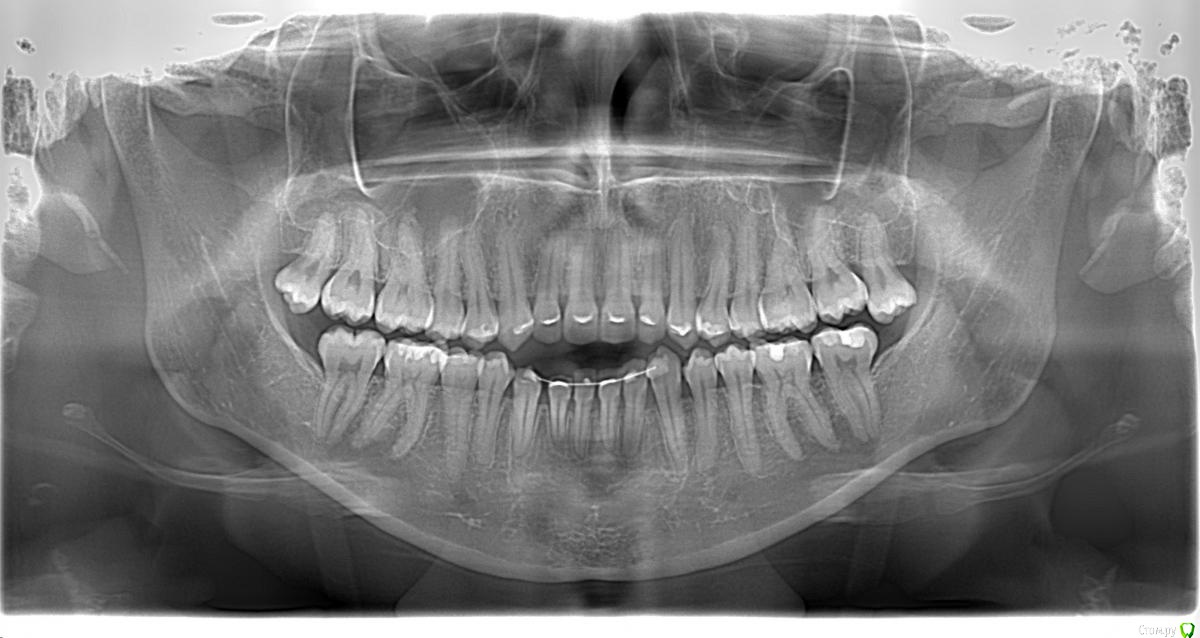

Opdihatop Опубликовано 4 марта, 2017 Поделиться Опубликовано 4 марта, 2017 И снова здравствуйте, коллеги. Вот такой вот случай к рассмотрению. Много лет назад пациентка уже проходила "камуфляжное" лечение. Со слов пациентки оно было закончено с передним открытым прикусом. Сейчас ситуация такая. Пациентка думает над ортохирургией, но меня смущает фронт н/ч. И по снимкам и по ситуации во рту корни 32, 31, 42, 43 зубов фенестрировали лингвальную кортикалку почти на всем протяжении, 33 - вестибулярную. Вопрос вот в чем: что делатьс этими зубами? Возможно ли их поставить на место? Или лучше не трогать, дольше простоят? Ссылка на комментарий

Brigita Опубликовано 4 марта, 2017 Поделиться Опубликовано 4 марта, 2017 она, кстати, везде язык прокладывает на фото. Наверно и в хирургии смысла не будет... Ссылка на комментарий

Opdihatop Опубликовано 29 мая, 2017 Автор Поделиться Опубликовано 29 мая, 2017 Как? Очень просто, "ДОЛЕЧИВАТЬ"! Тут фенестрация произошла из-за невылеченного инфантильного типа глотания и очень качественного (тут без сарказма) несъемного ретейнера. Исправь прошлый доктор язык, или поставь ретейнер хуже, так чтобы он его давление не выдержал и сломался, было бы все иначе. Ссылка на комментарий